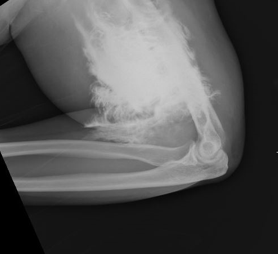

A 63 yo F is brought in by EMS after being found down. She has multiple ecchymoses on her chest and b/l flanks. GCS is 6. After intubation, she is taken for CT head/cervical spine and a CT chest/abdomen/pelvis with contrast. Upon return from CT, X-rays are done (shown below) to further evaluate bruising and a laceration to her L elbow. What's the diagnosis? (scroll down for answer)

Answer: Contrast extravasation